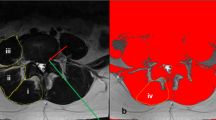

Pre-operative T2-weighted clinical magnetic resonance images (MRIs) (n = 54) were obtained of the lumbar spine within the 6-months preceding surgery. All images were obtained using a 3 T MRI system (GE MR 750, GE Healthcare, Waukesha, WI, USA) and a spine array coil. Subjects were positioned head-first, supine and centered at the umbilicus. Axial multi-slice 2D images were obtained using the following imaging parameters: slice thickness = 8 mm with 0 gaps and 22 slices covering the entire lumbar spine from L1-S1, acquisition matrix = 128 × 128, FOV = 256 × 256 mm [2]. Open-source MRI processing software (Horos) was used to view and analyze axial MRI images. Muscle tissue was collected at a standardized anatomical location 1 cm lateral to the spinous process at the spinolaminar border at the level and side of primary pathology as previously described [10]. For patients with bilateral symptomatology, biopsies were obtained on the side of surgeon’s approach preference, and location level was verified using intraoperative fluoroscopy. Biopsy locations were matched to the MRI slice closest to the inferior vertebral endplate at the biopsy level for further analysis. Regions of interest (ROIs) were drawn to include the whole multifidus muscle compartment by a single rater who was present for the surgical procedure. The image assessor was a graduate student with training in image processing and spinal anatomy. These ROI methods have been previously described in detail and have been shown to have high inter- and intra-rater reliability with individuals of similar experience and training [53]. Images were analyzed for total multifidus compartment cross sectional area (CSA), lean muscle cross sectional area (M-CSA), fat cross sectional area (F-CSA), and proportion of fat within the muscle compartment (FF) using custom MatLab software (Fig. 2).

MRI Image Processing. Multifidus cross-sectional area and fat fraction were determined using custom MatLab code to differentiate between muscle and fat. Regions of interest were drawn around the right and left multifidus in T2-weighted axial MRIs of the lumbar spine (a). Right and left multifidus were evaluated for muscle size (b), then, a bi-gaussian distribution of voxel intensity (c) was used to determine the intercept (red circle) between water (blue line) and fat (green line). The intercept is used as a threshold; greater voxel intensities are designated as fat and lower voxel intensities are designated as muscle. This analysis highlights muscle as teal and fat as yellow (d) and provides a calculation for both right and left multifidus cross-sectional area and fat fraction (d, table)